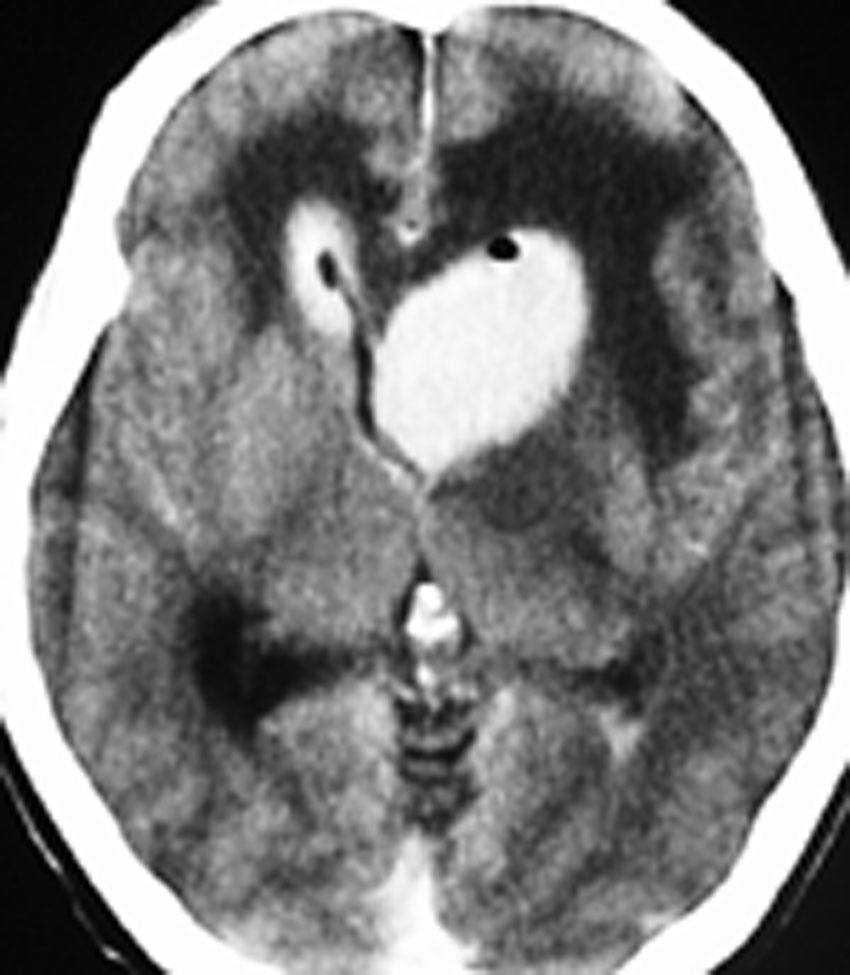

単純CT(左側の画像)で腫瘍の部分が少しだけ高吸収値域を示す(ちょっと白っぽくなる)のが大きな特徴で,この所見をもってグリオーマとの区別をします。周囲に黒っぽい部分がありますが,これは脳の腫れで脳浮腫と言います。右側のCTは造影剤を入れたものでよりはっきり写ります。